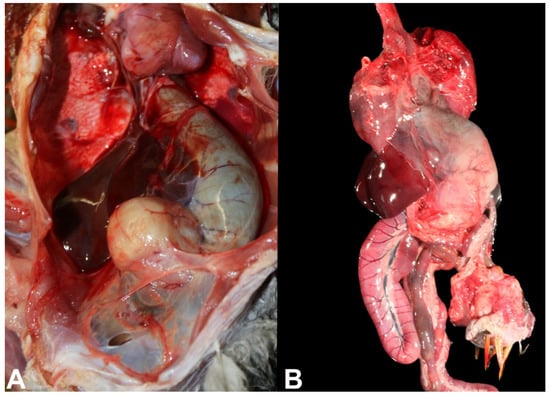

The most striking macroscopic finding in birds affected by PDD is a distended proventriculus (Figure 4A,B) [2,23] that is usually accompanied by marked thinning of the proventricular wall, which in severe cases, can rupture [24]. Similarly, if crop innervation is compromised, a dilated crop can also be identified in PDD birds, and it is usually associated with regurgitation [10]. However, not all birds will develop proventricular dilatation as they may have only the CNS affected, and, therefore, will only manifest central neurological signs. In these cases, no gross lesions are observed in the brain or spinal cord.

Figure 4. Macroscopic lesions of PDD in psittacine birds. (A) Thin-walled distended proventriculus in the coelomic cavity of a red-and-green macaw hybrid (Ara chloropterus). (B) Ex situ thin-walled distended proventriculus of a Catalina macaw.

Due to the progressive and chronic nature that usually characterizes PDD, cachexia is frequently observed due to impairment gastrointestinal motility. Consequently, carcasses of birds affected by PDD typically have poor body condition scores. Cardiomegaly and/or hydropericardium can be observed in birds with sudden death [19].